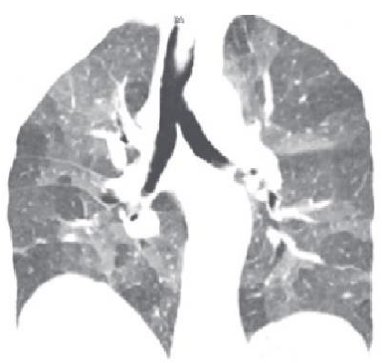

A tomografia computadorizada de tórax deve ser solicitada para todos os pacientes com suspeita de doença intersticial pulmonar. Avalie a imagem a seguir:

Enunciado 2170306-1

O padrão tomográfico é mais compatível com pneumonia: